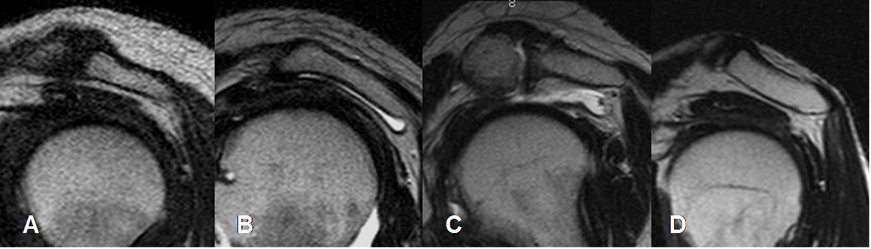

Fig 27. Labrum normal.

A, B, C y D: RM axial en FFE. Distintas configuraciones normales del labrum anterior.